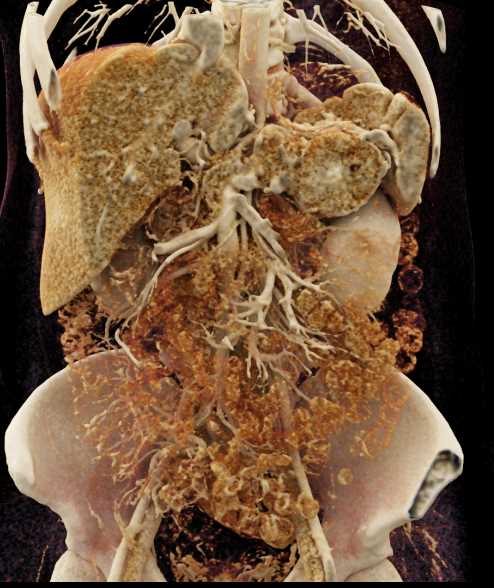

Neuroendocrine Tumor Pancreas